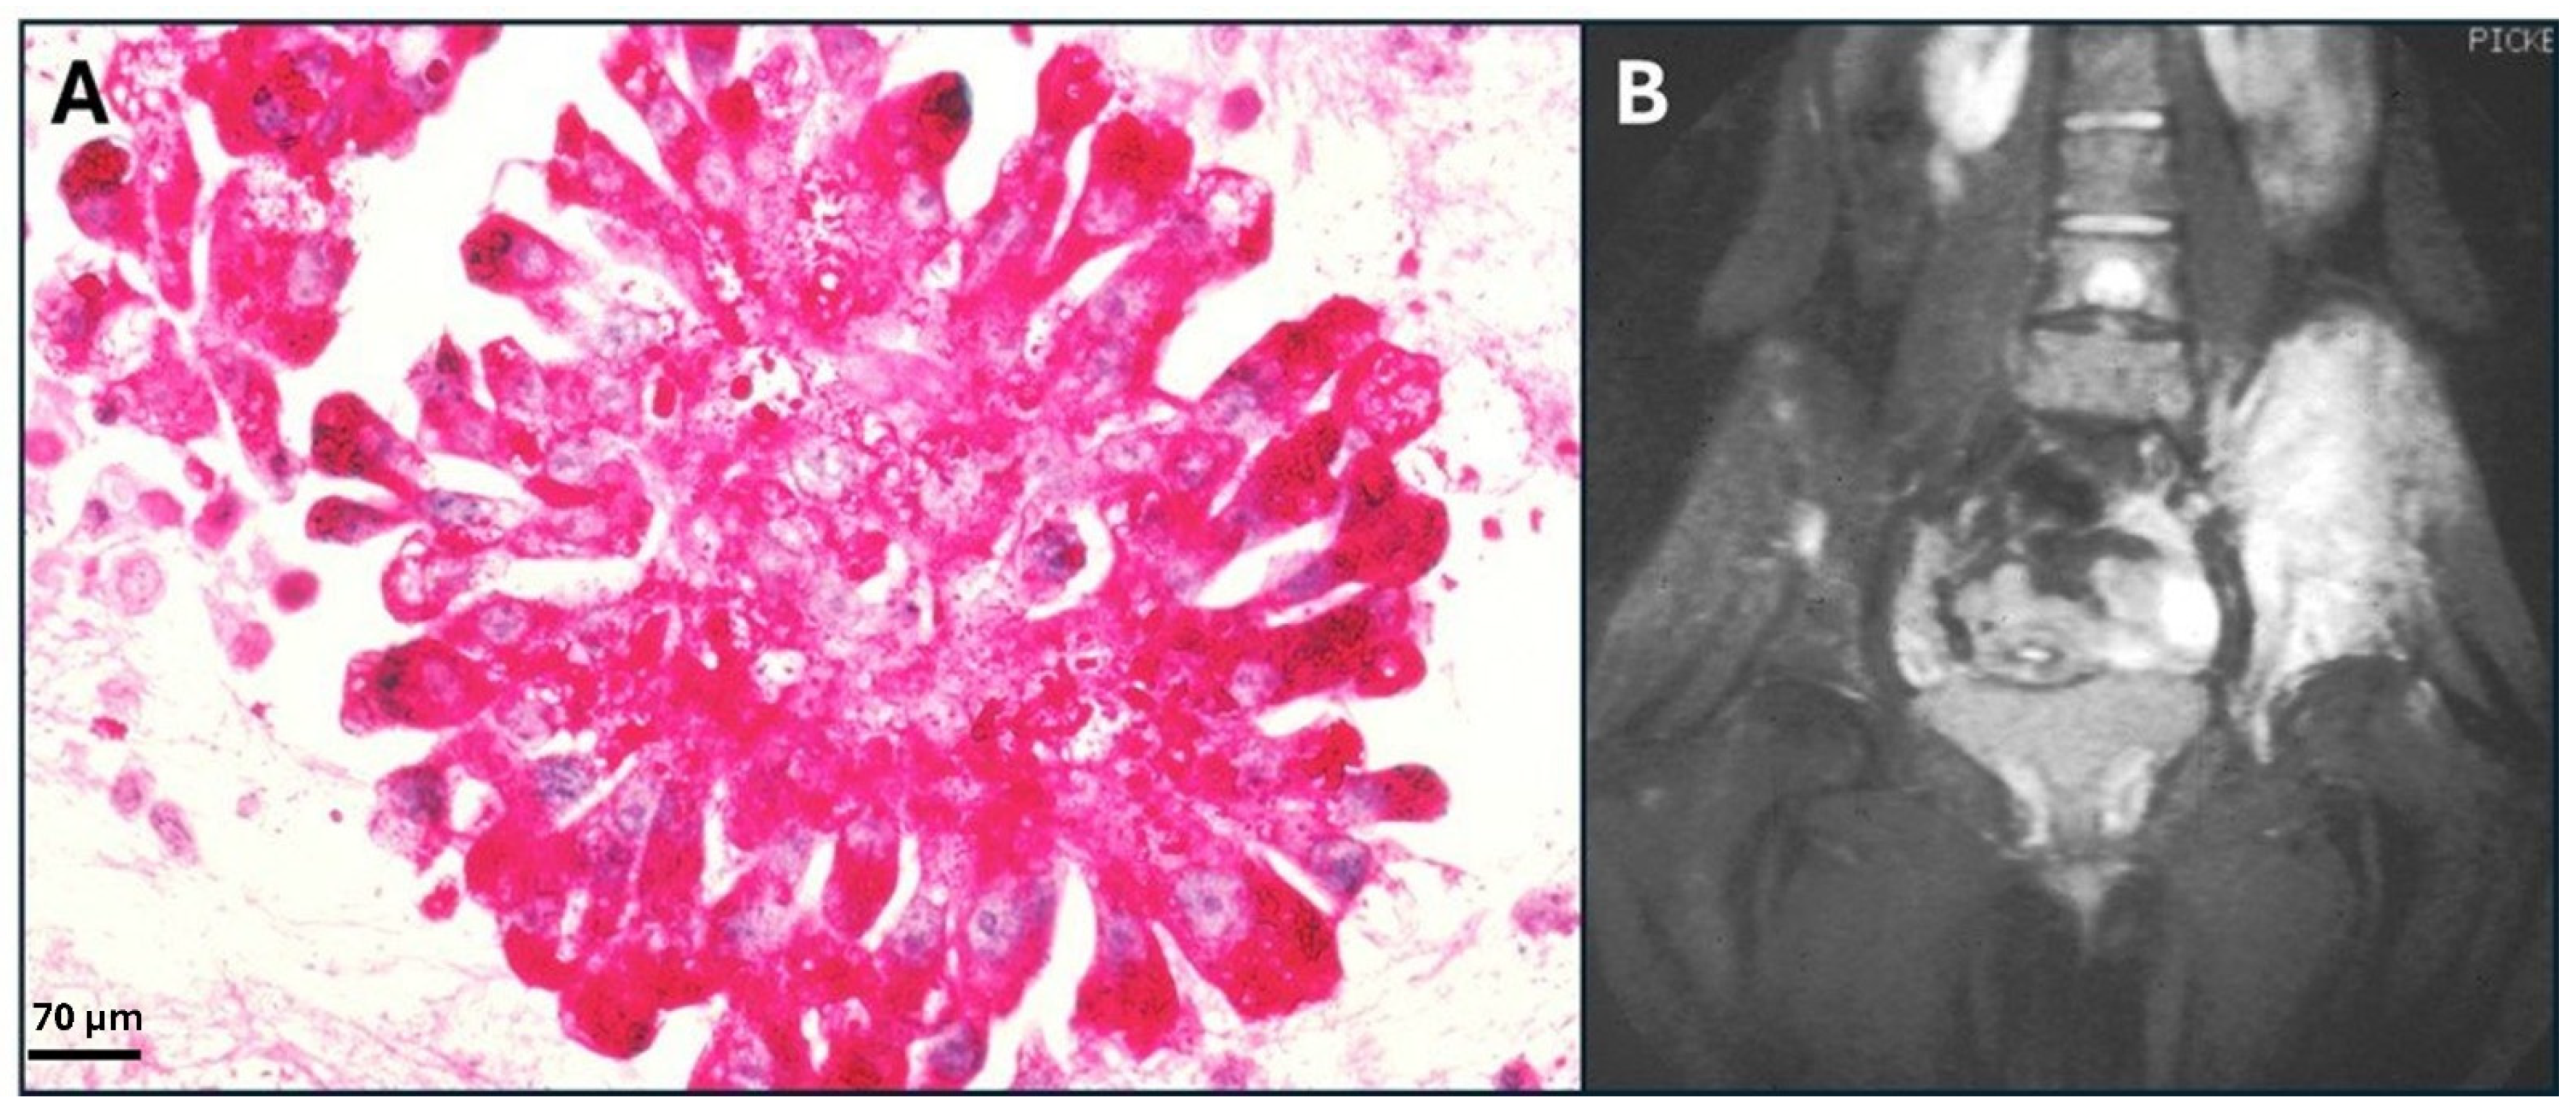

- Ewing’s Sarcoma in the Pleural Fluid: Image Details—NCI Visuals Online. Available online: https://visualsonline.cancer.gov/details.cfm?imageid=2327 (accessed on 13 December 2024).

- MRI of Ewing’s Sarcoma: Image Details—NCI Visuals Online. Available online: https://visualsonline.cancer.gov/details.cfm?imageid=1832 (accessed on 13 December 2024).

- Durer, S.; Gasalberti, D.P.; Shaikh, H. Ewing Sarcoma. In StatPearls; StatPearls Publishing: Treasure Island, FL, USA, 2024. [Google Scholar]

- Zöllner, S.K.; Amatruda, J.F.; Bauer, S.; Collaud, S.; de Álava, E.; DuBois, S.G.; Hardes, J.; Hartmann, W.; Kovar, H.; Metzler, M.; et al. Ewing Sarcoma—Diagnosis, Treatment, Clinical Challenges and Future Perspectives. J. Clin. Med. 2021, 10, 1685. [Google Scholar] [CrossRef]